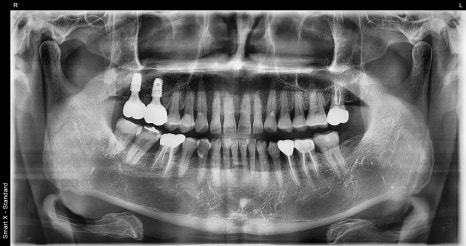

파노라마 검사와 CT 촬영을 통해

정밀 확인을 진행했습니다.

이후 약 2~3개월 간 잇몸뼈가 안정되는 기간을 거쳤고,

체크 내원 시 파노라마 검사에서

임플란트가 잘 자리 잡고 있는 것을 확인했습니다.